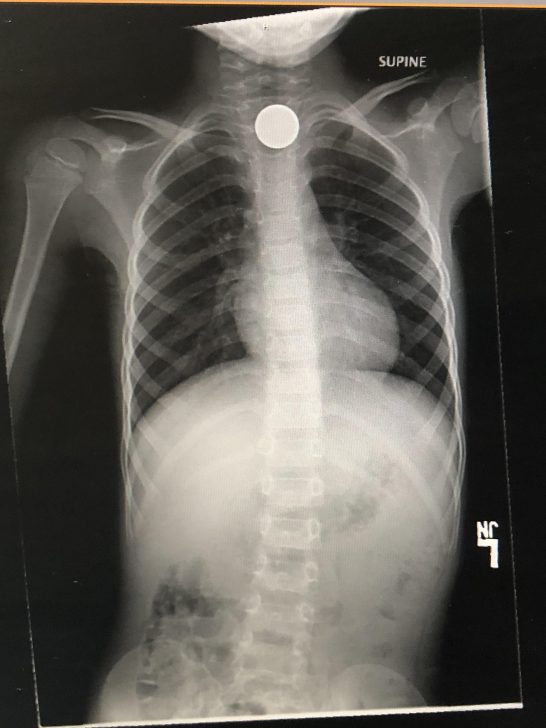

„A fiam lenyelt egy érmét. 4400 dolláromba került.”